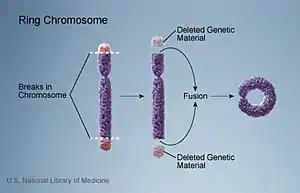

Ring chromosome 18 is a genetic condition caused by a deletion of the two ends of chromosome 18 followed by the formation of a ring-shaped chromosome. It was first reported in 1964.[2]

Genetic

Individuals with ring 18 have one of their two copies of chromosome 18 that has formed the shape of a ring. The ring is formed when the caps on both the long arm (q) and the short arm (p) of one copy of chromosome 18 are lost and the new ends re-join to form the ring. Because the ring involves deletions of both the long arm (18q-) and the short arm (18p-) of chromosome 18, individuals with ring 18 can have features of both 18p- as well as distal 18q-.

The phrase “ring 18” refers to the shape that the normally linear chromosome assumes when one tip of the chromosome joins the other. A ring-shaped chromosome is the result. In the case of ring 18, one of the two copies of chromosome 18 has formed a ring.